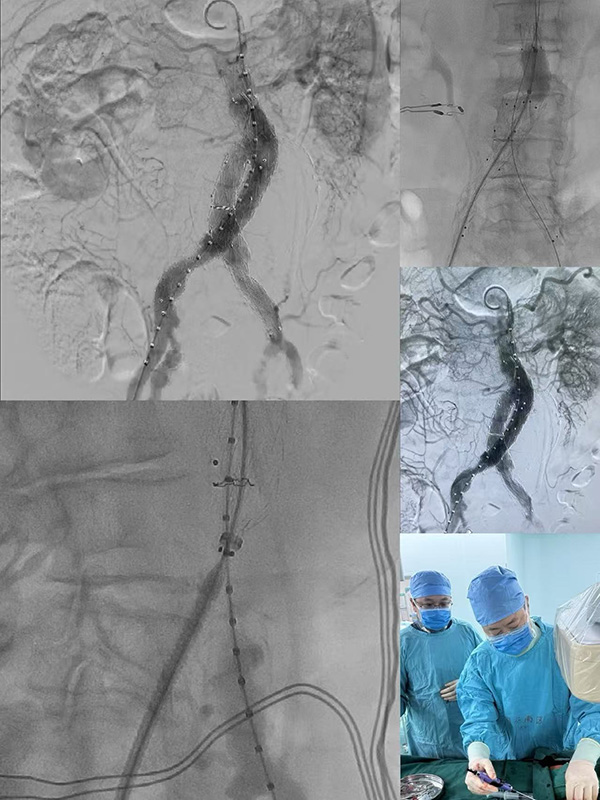

国庆假期,最新老虎机,新老虎机平台同仁医院医护团队坚守手术灯下,成功为挽救了一名巨大腹主动脉瘤患者与的生命。

巨大腹主动脉瘤如同体内的“不定时炸弹”,随时可能破裂引发致命风险,手术容不得半分差错,最新老虎机,新老虎机平台医院血管外科冯亚平教授团队和麻醉科、手术室医护团队术前反复制定手术方案,将术中可能出现的风险点纳入预案。

手术开始,主刀医生凝神专注,在毫米间精准操作,麻醉医师、护士、技师各司其职,默契配合。

一小时后,手术顺利完成。当手术门缓缓打开,医护人员第一时间走向等候的家属:“手术很成功,放心吧!”简单一句话,让内心紧绷的家属瞬间红了眼。